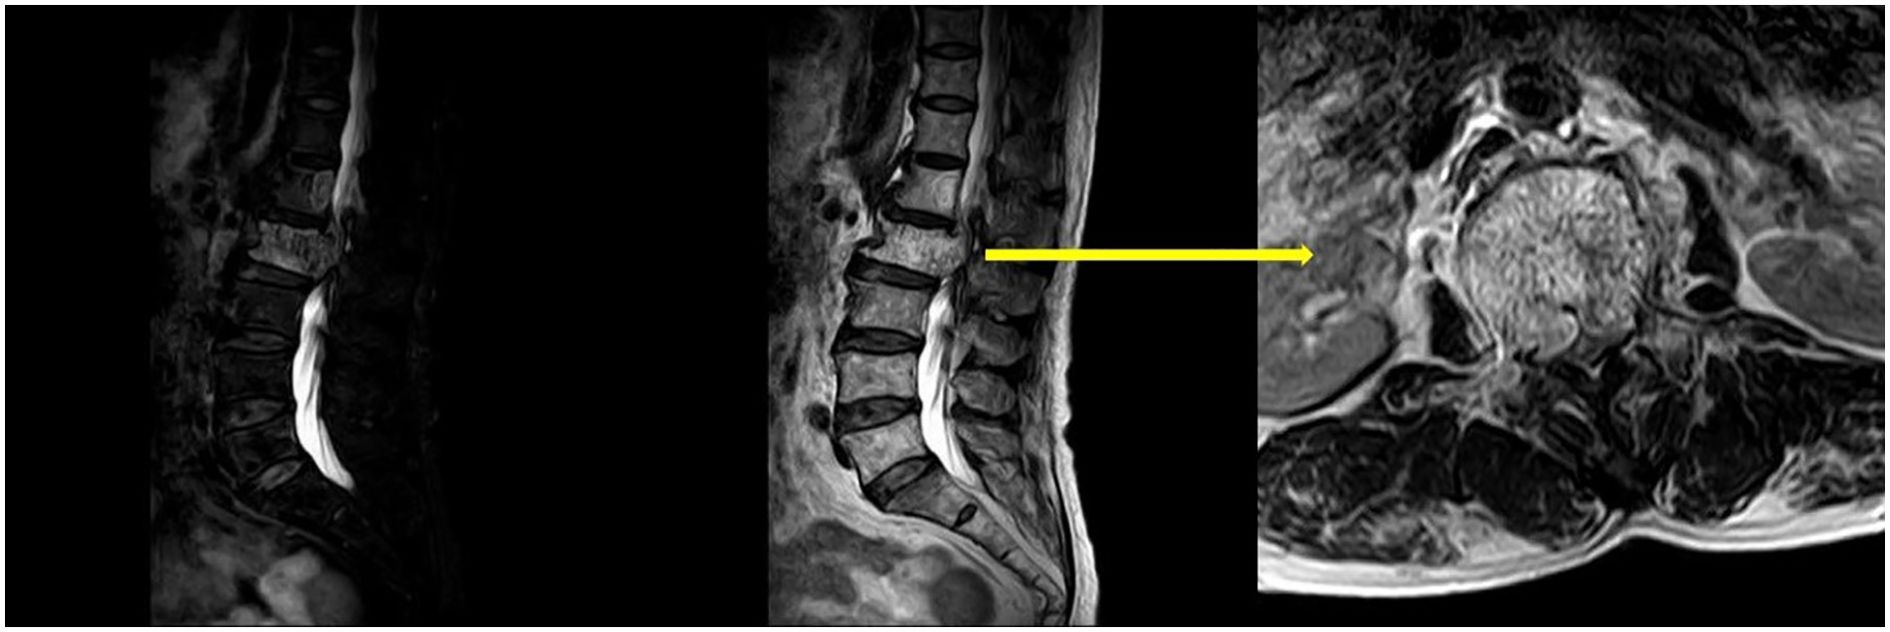

Upon physical examination, tenderness and percussion pain were observed in the L1 and L2 spinous processes, with radiating pain in both lower limbs. Bilateral iliopsoas muscle strength was graded as IV. The strength of the other muscle groups remained normal. The lumbar extension test was positive, and bilateral Babinski signs were negative. The mean preoperative visual analog scale (VAS) was 8. Preoperative lumbar CT revealed a mass with abnormal density in the L2 vertebral body and posterior elements, with vertebral body deformation and spinal stenosis, and within the L1 vertebral body and left posterior elements (Figure 1). Preoperative lumbar MRI revealed patchy T1 hypointensity and T2 hyperintensity on the left side of the L1 vertebral body and posterior elements, with high signal on fat-suppressed sequences. The L2 vertebral body was slightly flattened, with posterior bulging of the vertebral body margin. The vertebral body and bilateral posterior elements demonstrated T1 hypointensity and T2 hyperintensity, with high signal on fat-suppressed sequences, and the corresponding spinal canal was significantly compressed, narrowed, and deformed. Heterogeneous signals were observed within the spinal canal at the L1-L2 level, with compression and displacement of the cauda equina (Figure 2). Preoperative lower-limb electromyography was performed to further quantify the degree of bilateral lower extremity neurological dysfunction and to assist in differential diagnosis. The results revealed reduced motor conduction wave amplitude of the bilateral common peroneal nerves, a lack of definite waveforms induced by the right common peroneal nerve F-wave, and abnormal spontaneous electrical activity in the bilateral gastrocnemii, right tibialis anterior, and tibialis posterior muscles, with partial widening of the Motor Unit Potential duration in the right tibialis posterior muscle. The preoperative diagnosis was AVH at L1 and L2 (Enneking stage 3).

Figure 2. Preoperative lumbar MRI revealed that AVH had invaded the spinal canal and was compressing the spinal cord.